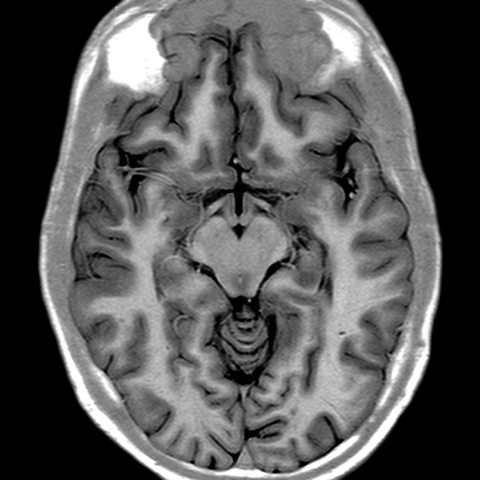

Cerebral Hemispheres, MR (normal) [4 of 9]